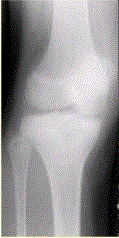

患者男,15岁。右膝X线平片和CT检查见下图。病变发生部位是A.骨端B.干骺端C.骨骺D.骨干E.关节腔

问题 患者男,15岁。右膝X线平片和CT检查见下图。 病变发生部位是

选项 A.骨端 B.干骺端 C.骨骺 D.骨干 E.关节腔

答案 C